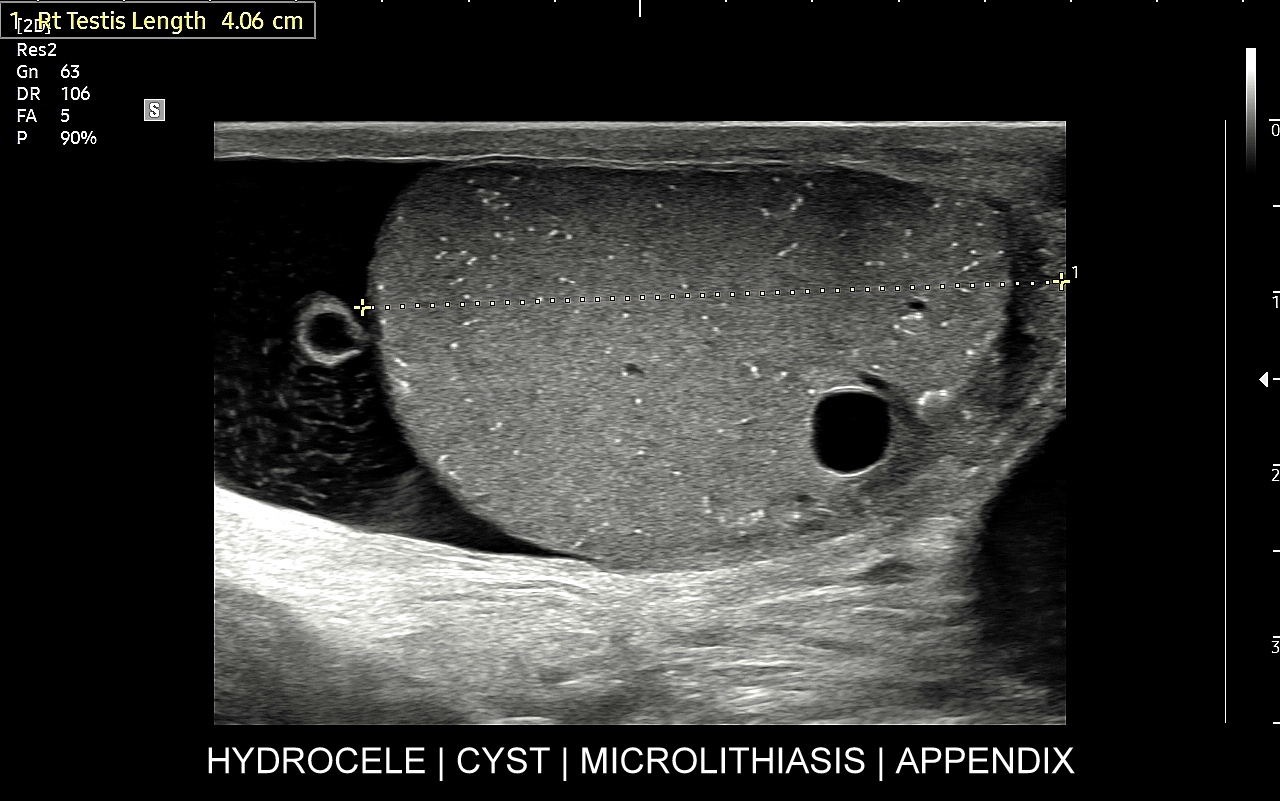

USG moszny i kanału pachwinowego jest podstawową metodą obrazowania jąder, najądrzy, powrózka nasiennego, w tym nasieniowodu oraz towarzyszących im naczyń żylnych i tętniczych. Badanie USG przeprowadzić należy w przypadku wystąpienia bólu i obrzęku jąder, pojawienia się macalnego guzka w obrębie moszny, podejrzenia skrętu lub zapalenia jądra, żylaków powrózka nasiennego, w ramach oceny dojrzewania płciowego chłopców. Kanał pachwinowy bada się także w sytuacji podejrzenia wnętrostwa, przepukliny pachwinowej, w celu oceny węzłów chłonnych, a także nasieniowodu w diagnostyce niepłodności męskiej.

Mosznę bada się aparatem USG wyposażonym w dedykowaną sondę o wysokiej rozdzielczości przeznaczoną do oceny jąder i drobnych struktur moszny, koniecznie z zastosowaniem trybów dopplerowskich, takich jak Doppler kodowany kolorem, Doppler spektralny i obrazowanie mikrounaczynienia. Dopełnieniem badania USG jąder jest użycie w stosownych przypadkach trybu elastografii oraz trybu USG z kontrastem (CEUS). Lekarzem, który pierwszy we Wrocławiu i na Dolnym Śląsku przeprowadził badanie CEUS jąder jest dr Tomasz Szczepański.

Najczęstsze choroby w obrębie moszny obejmują żylaki powrózka nasiennego, zapalenia jąder i najądrzy, wodniaki jądra, skręty szypuły jądra bądź przydatków jądra, torbiele najądrzy, nowotwory i raki jąder. Niezależnie od powyższego u chłopców spotyka się wnętrostwo, czyli niepełne zstąpienie jądra do moszny, które to może pozostać w jamie brzusznej lub pachwinie, a także ektopię jąder, czyli ich zabłąkane położenie (np. w okolicy krocza).